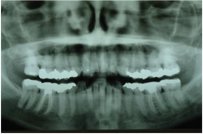

Early Orthodontics (The "Magic Window" Ages 8–10)

Starting orthodontic care young can guide jaw development, address crowding or bite issues, and sometimes reduce the need for treatment later. We recommend an assessment if your child has missing adult teeth, spacing concerns, or an over/underbite.